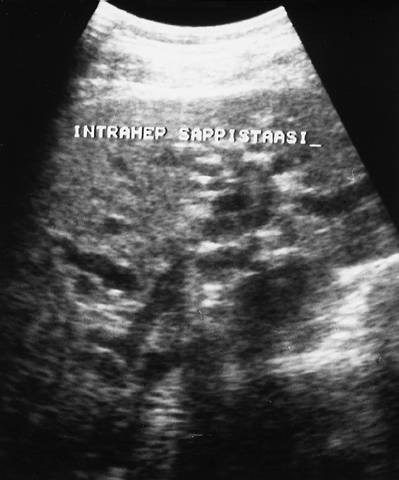

Kuva 1.

Haimasyöpä.

Maksan UÄ-tutkimuksessa nähdään laajentuneita intrahepaattisia sappitiehyitä, kuvassa tummina putkimaisina muodostumina.